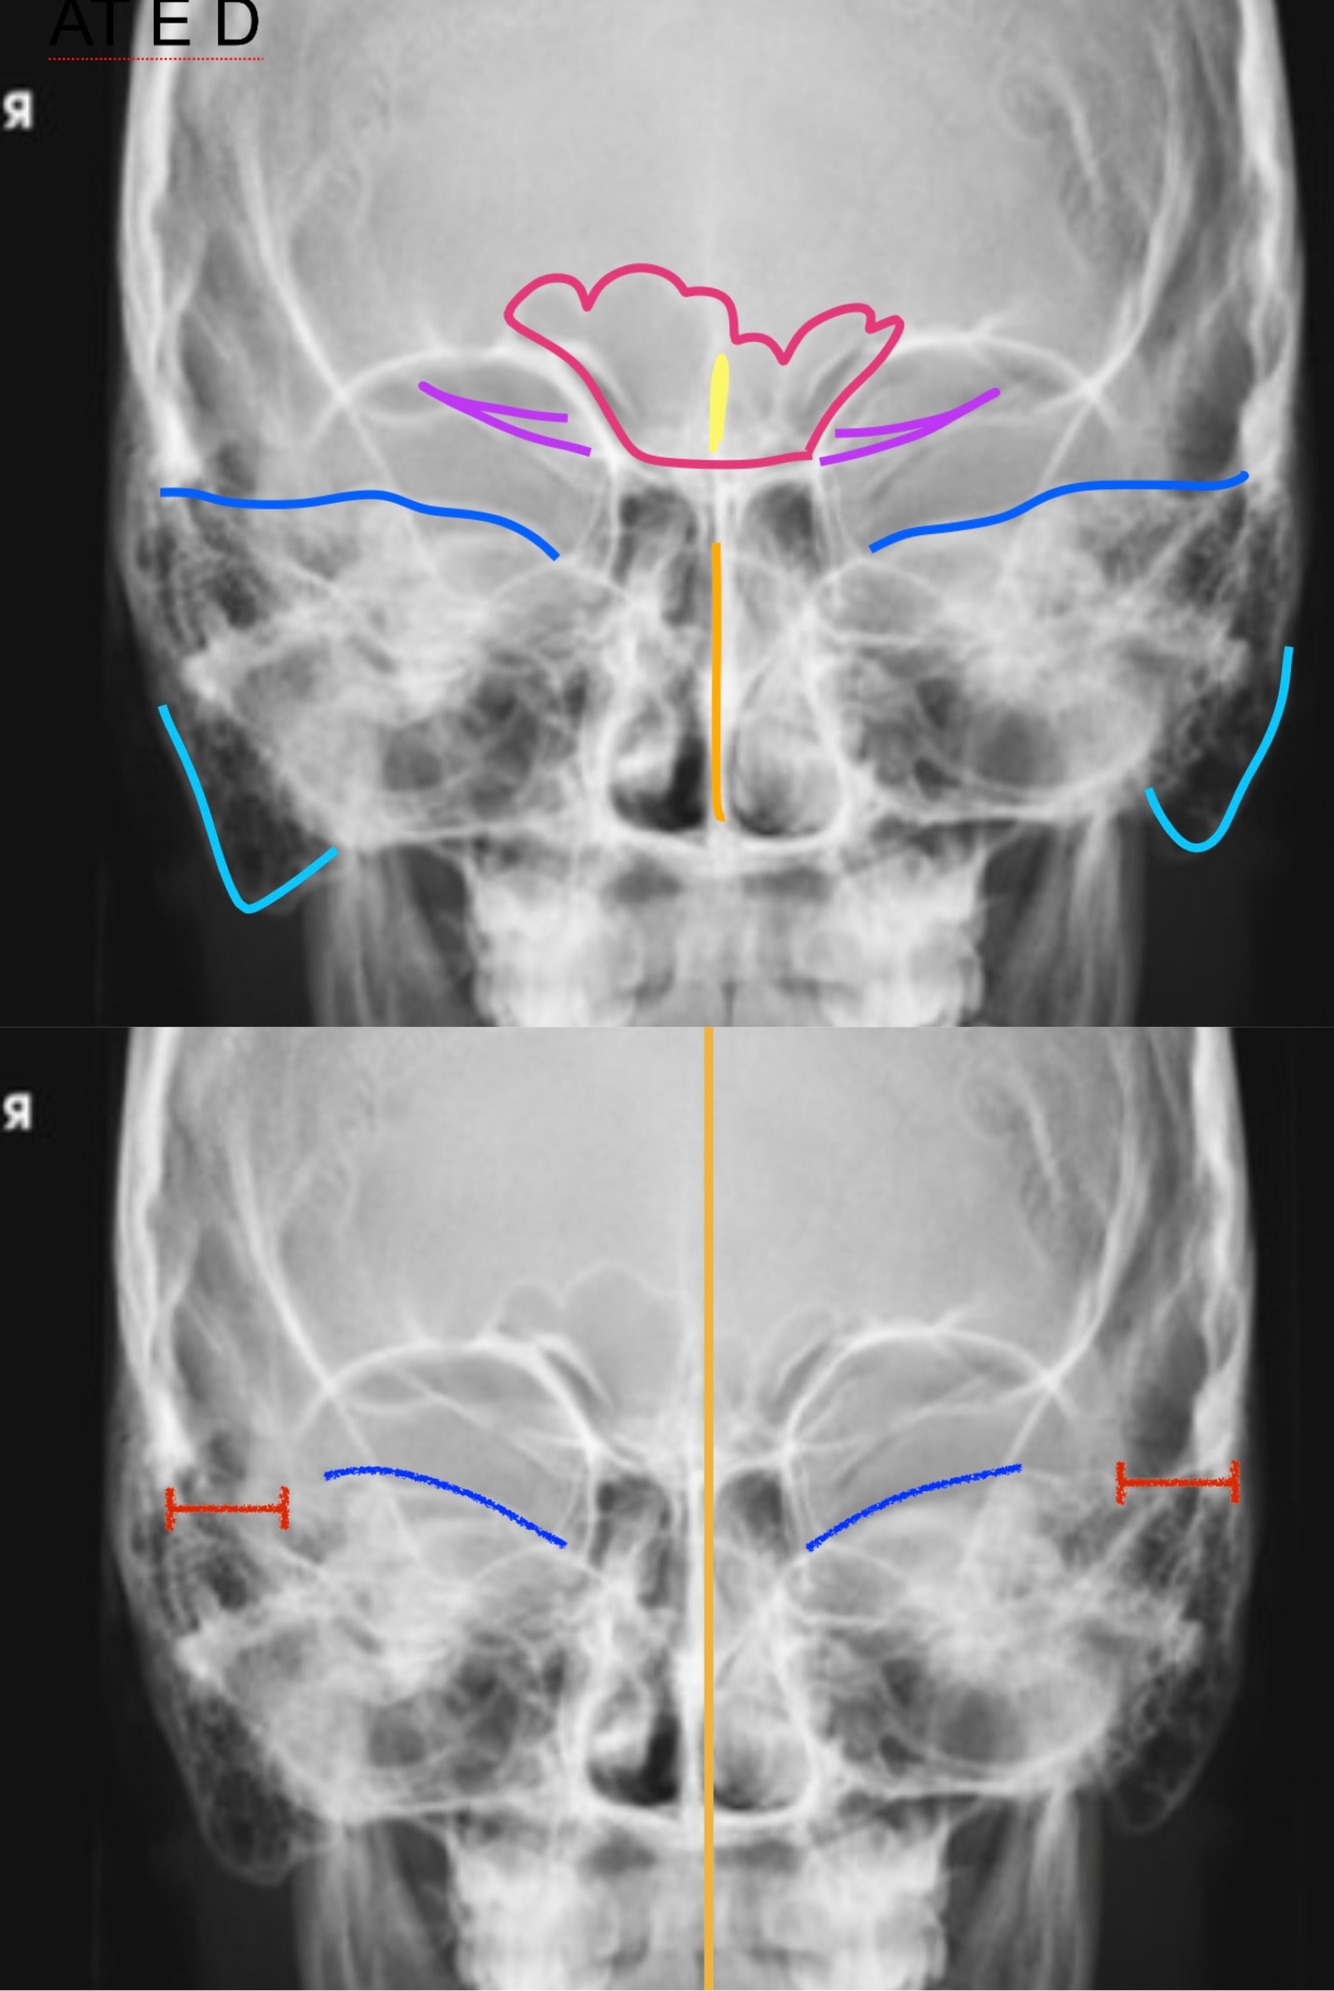

PA AXIAL CALDWELL Positioning

A

-Rest tip of nose on grid device and center the nasion to the IR so the OML forms a 15 degree angle OR tilt the grid down 15 degrees

-CR: perpendicular exiting the nasion

-SID: 40”

-Adjust the MSP perpendicular to the IR

-Respiration: suspend

14

Q

PA AXIAL CALDWELL Evaluation Criteria

-Proper collimation

-Frontal sinuses lying above the frontonasal suture and anterior ethmoid cells lying above petrous ridges

-No rotation or tilt

-Equal distances from lateral borders of skull to lateral borders of orbits

-Symmetric petrous ridges

-MSP of cranium aligned with long axis of field

-Petrous pyramids in lower 1/3 of orbits